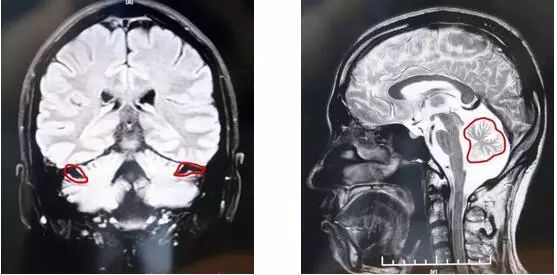

统计资料显示,全先进每年约有1500万人死于各种与脑萎缩相关的疾病。而随着全球人口老龄化趋势的显现,死亡率也将呈高发态势,亟待引起各方重视。小脑是人体重要的器官,控制身体和四肢的肌肉协调、走路时身体的平衡、动作的平顺、说话的清晰度、吞咽的顺畅及眼球的运转等。而小脑萎缩是一组以共济失调为主要表现的中枢神经系统疾病。